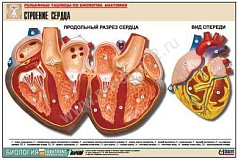

Комплект включает в себя 21 таблицу следующего содержания:

19. Строение сердца;